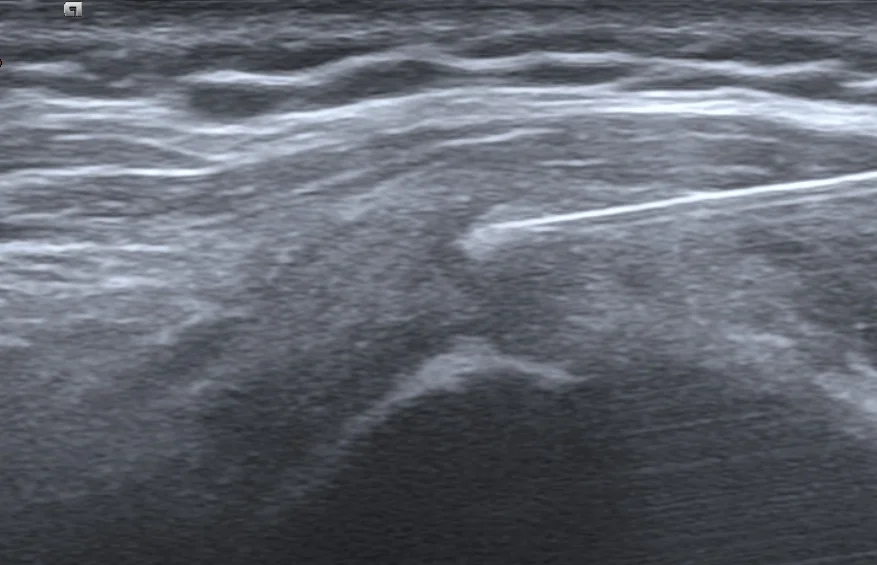

治療過程中,螢幕上的畫面就像是挖掘工程。一開始那顆巨大的白色結石,隨著我們不斷地沖洗、抽出粉筆灰般的鈣化物,體積肉眼可見地開始縮小、崩解。患者看著螢幕,驚訝地說:「原來裡面真的有這麼多東西!」

到了治療尾聲,那顆原本巨大的「路障」,幾乎已經看不到了。